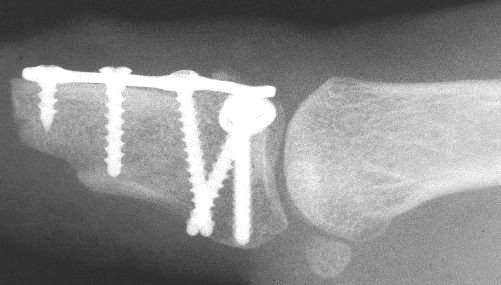

Late Xrays.